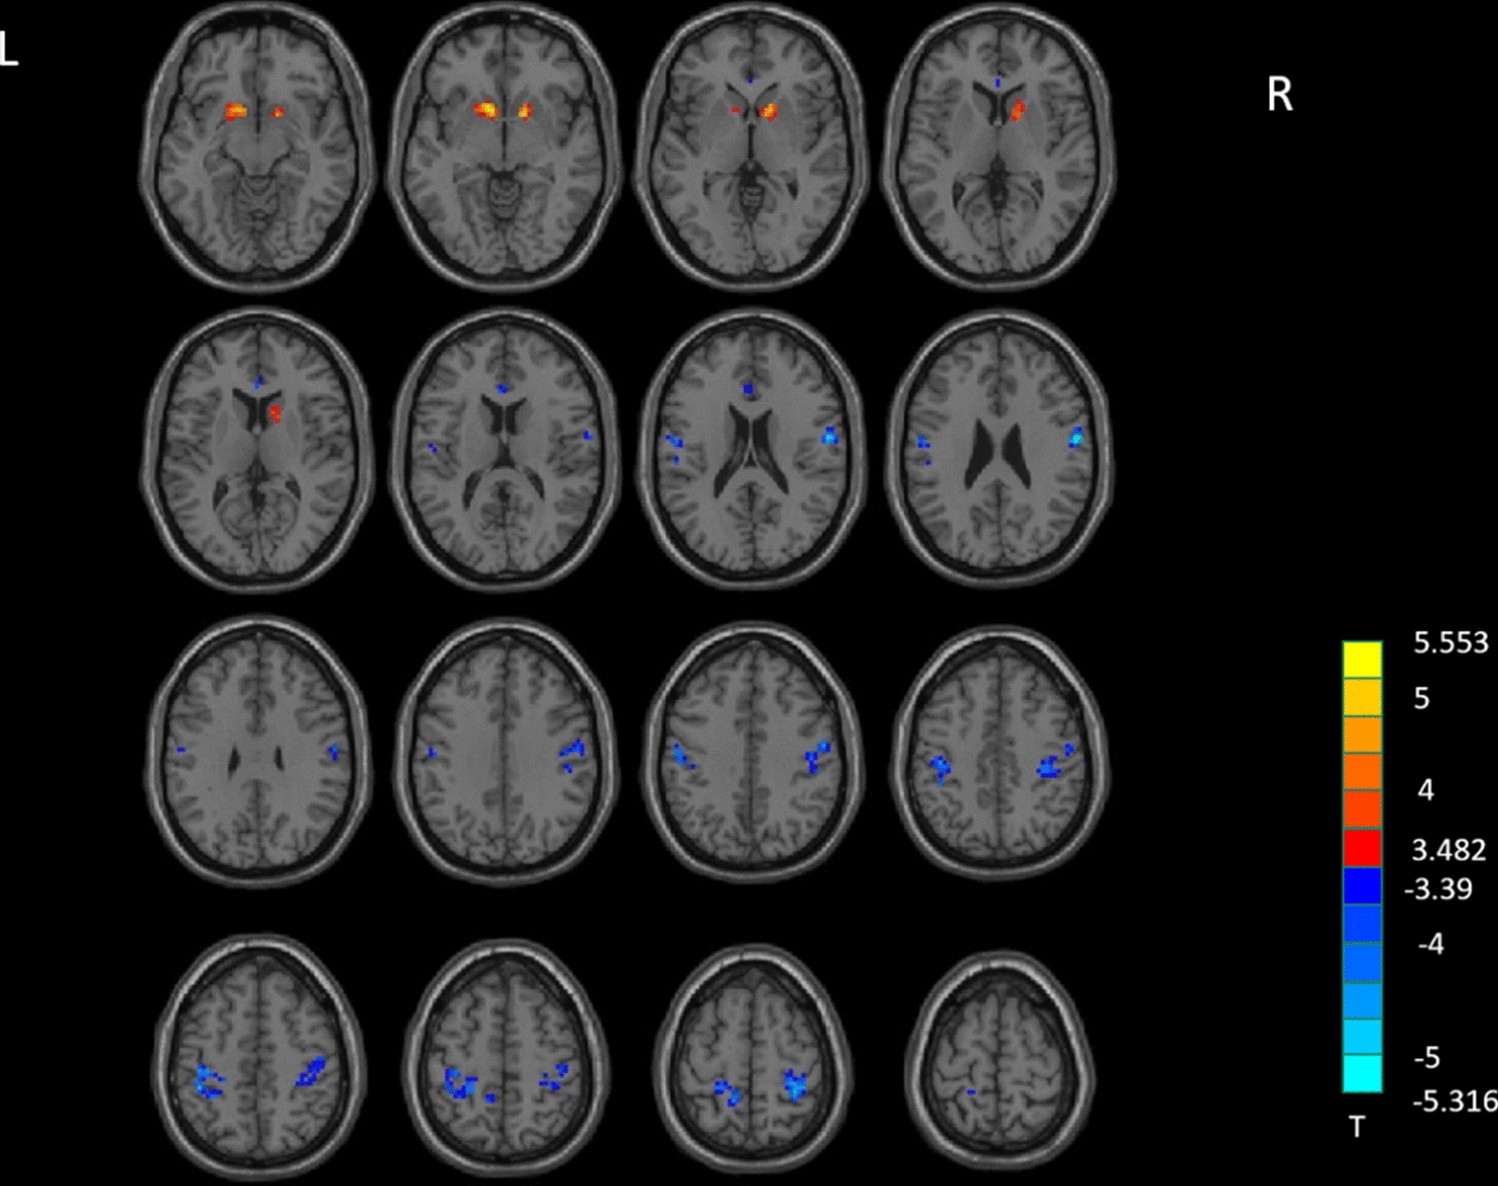

Figure 2

ReHo analysis. Two-sample t-test results are presented, voxel level p < 0.001, cluster level p < 0.05, two-tailed, voxel size > 29, corrected by GRF. Area in blue with significantly decreased ReHo value; area in yellow and red with significantly increased ReHo value. Created with DPABI_V4.3_200401 (http://rfmri.org/dpabi).